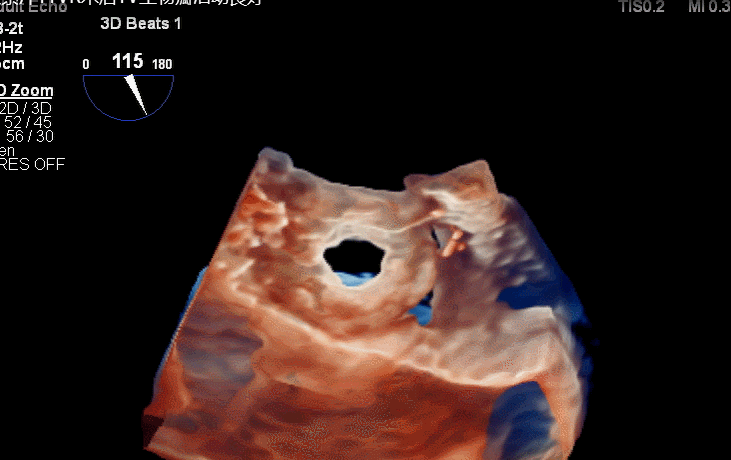

食道超声评估

三尖瓣术前平均压差9mmHg

三尖瓣瓣中瓣术后平均压差3mmHg

术后三维超声同时显示MV机械瓣及新的TV生物瓣